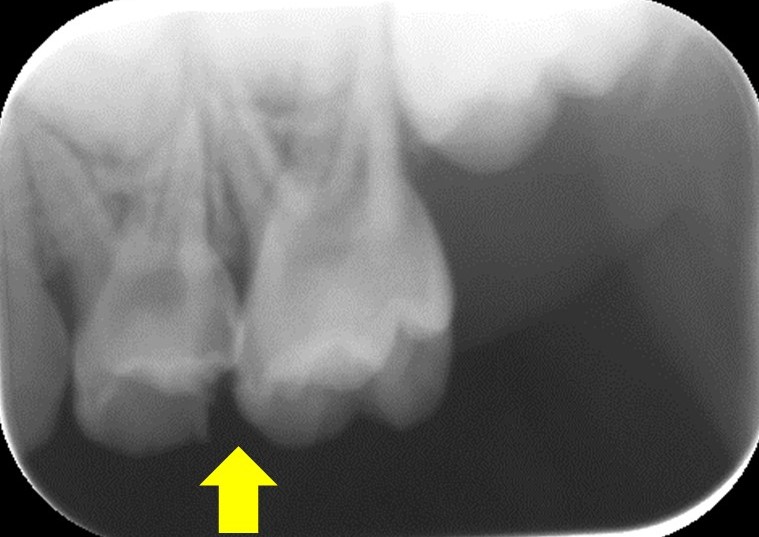

そんなお子さんに特徴的なのは虫歯の部位です。大半は奥歯の歯と歯の隙間に虫歯ができてくるケースが非常に多いのです。

なぜならお口の汚れは奥歯と奥歯の隙間にも停滞するからです。

歯と歯の間の汚れはフロスを通さないと完全に取れませんし、もともと子供の歯は大人よりも隙間が開いていることが多いので、どうしても汚れが停滞しやすく、磨き切れていなく、虫歯になってしまいやすいのです。